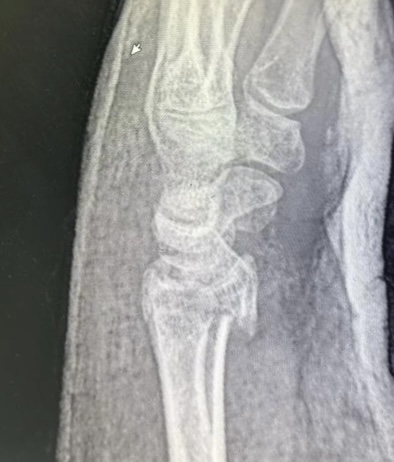

Клинический случай: внутрисуставной перелом дистального метаэпифиза лучевой кости — до операции